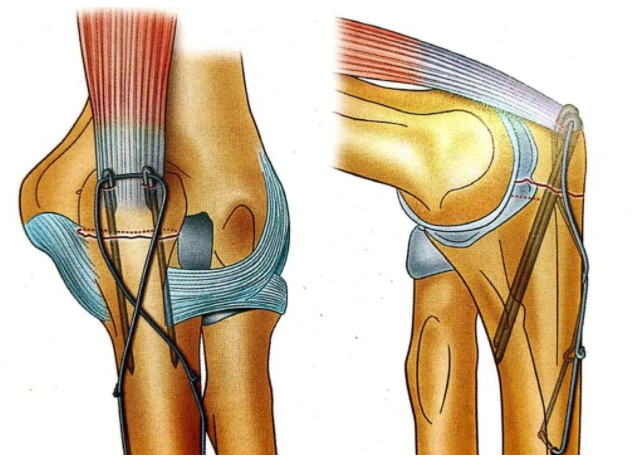

張力帶固定(ding)技術

確認骨折穩定性(xing)及關節(jie)活(huo)動(dong)度,包括旋前(qian)旋后(supination-pronation)活(huo)動(dong);排除克(ke)氏針穿入肱尺關節(humeroulnar)或(huo)橈尺關節(radioulnar joint)的可(ke)能性;術后(hou)影像學需(xu)顯示骨折復位良好、內固定位置(zhi)正(zheng)確。